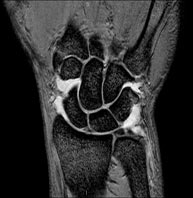

- RM Rodilla

Exploración para el estudio de lesiones en la articulación, como roturas meniscales y de ligamentos cruzados (unicamente detectables mediante esta prueba), condropatía o desgaste del cartílago y multitud de otras alteraciones derivadas de la actividad deportiva y los cambios degenerativos (osteoartrosis). Tiene una duración aproximada de 18 minutos. No emplea radiación ionizante.

- Artro-RM Rodilla

Exploración para el estudio de las lesiones en pequeñas estructuras anatómicas de la articulación, tales como cartílago y meniscos, principalmente los ya operados. El estudio viene precedido por una inyección de contraste en el interior de la articulación, realizada bajo control de rayos X. La duración global de los dos procedimientos es de 50 minutos.